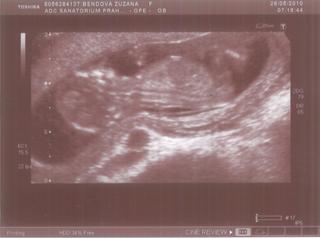

Dnes mám hot news, po měsíci jsem byla na kontrole na gyndě a super, vše se zdá v pořádku, miminko má nožičky, ručičky, točilo se mi v břiše jak na kolotoči, prostě hyperaktivní akrobat! To bude prostě celý manža! Já jsem větší kliďas! A dokonce na nás vystrkoval prdelku, no je brzo to určovat, ale pak doktor tipuje spíš kluka. Jo a jsme v 13+2. A vracím se do práce, protože jsem už zdravá, žádné omezení 😅 😀

Přikládám fotečku z UTZ:

@blondy: chtěla jsem se ještěš zeptat, mám tam toho mimíse nějak stísněného, oproti fotkám, co mají ostatní holky... Fakt se tam chudáček hodně mačkal, to šlo vidět na tom ultrazvuku... Doktor říkal, že se ta děloha ještě roztáhne... Je to v pořádku???? Nemůžu s tím něco udělat? Vhudáček malinkej otlačenej 😅

Dudu, super fotka z ultrazvuku, je to macek koukám 😀 Je dobře, že je všechno tak,jak má být. Hele, chce se ti vůbec vracet do práce??? 😕 😀 co se týče mazání bříška a ostatních parití, tak já začla někde na 4.měsíci a vyhovoval mi olej z DM Babylove. Já mám všeobecne suchou pokojžku,tak se odjakživa mastím olejíčkama 😀 V létě hlavně olivovým, to je pak kůže krásně hnědá 😀 Strie se mi za celou dobu těhu vůbec neudělaly. Mazala jsem břuch,boky,zadek a stehna.Paradox je, že se mi udělaly hned po porodu na bocích a trochu na stehnech,ale mažu dále a je to lepší (tím samým olejem pro těhulky,oni to na něm i píšou,že se jím má ženská mazat ještě cca 3m po porodu myslím).

K tomu "mačkání", neboj, nic se mu nestane, někdo to prostě má. Jak tak koukám, máš podobné těhu jako já, já měla malou taky horzně zmáčklou, ještě na UTz ve 23tt tam měla chudinka hrozně skrčené nožičky u ručičky až mi jí bylo líto. Dr. mi řekl, že je to tím, jak mám pevné břišní svaly, že prosgtě tu dělohu nechtějí pustit. A nebpo to může být tím, že máš pevnou dělohu a že roste pomalu. Ale má to jednu výhodu, neměla by jsi mít velký břuch a měla by jsi brzy cítit pohyby. 😀